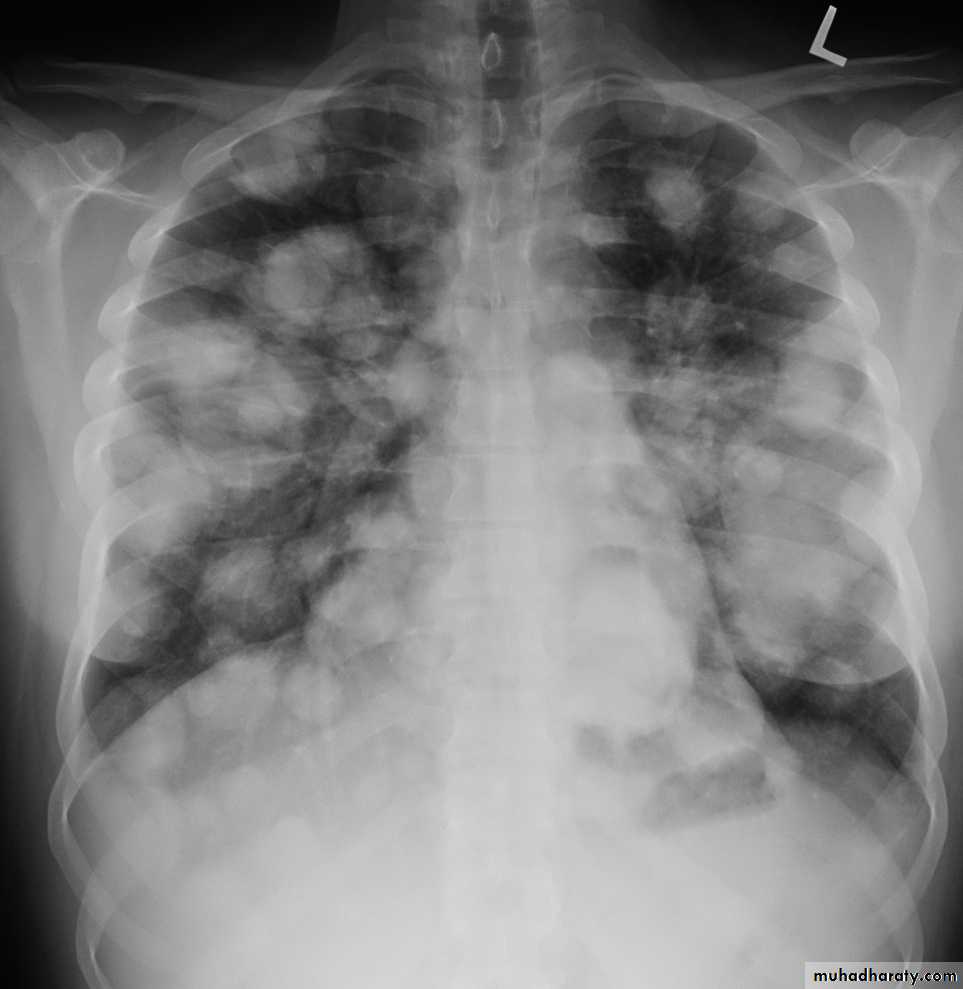

Metastisis to Lung (canon ball appearance)

CXR of adult, PA view shows Bilateral rounded radioopaque nodules of multiple sizes distributed all over both lung fields( Cannon ball appearance)